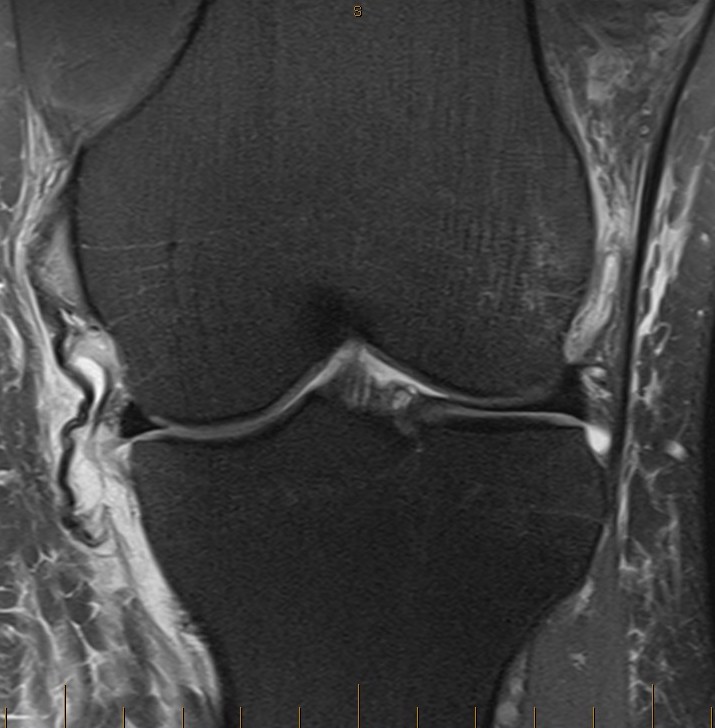

Tibial side: wave sign, ensure that the MCL is no flipped above pes anserinus as will not heal (analogous to Stener lesion)

Wave sign indicative of tibial avulsion, with ligament retracted above pes anserinus / hamstring tendons